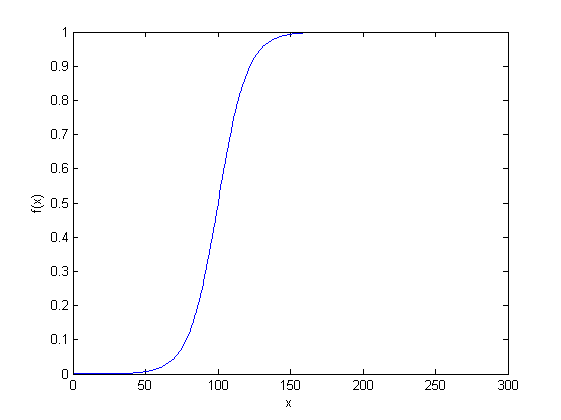

The sigmoid function refers to a special case of a logistic function as shown in Figure 3, defined by the equation:

| (1) |

where is the centre and is the slope control.

Every pixel in the segmented lumbar muscle region is subjected to the sigmoid function which gives a clear discrimination between the muscle region and the fatty region as shown in Fig. 4.

| (2) |

In the sigmoid function, choosing different values for the centre is associated with the threshold selection for discerning the fatty region from the muscle region. Similarly varying the values of slope control in the sigmoid function is associated with the softness level of the discerned fatty region edges. Pixel belongs to “fat”, if the pixel intensity is above the threshold selected by adjusting the centre value in the sigmoid function .